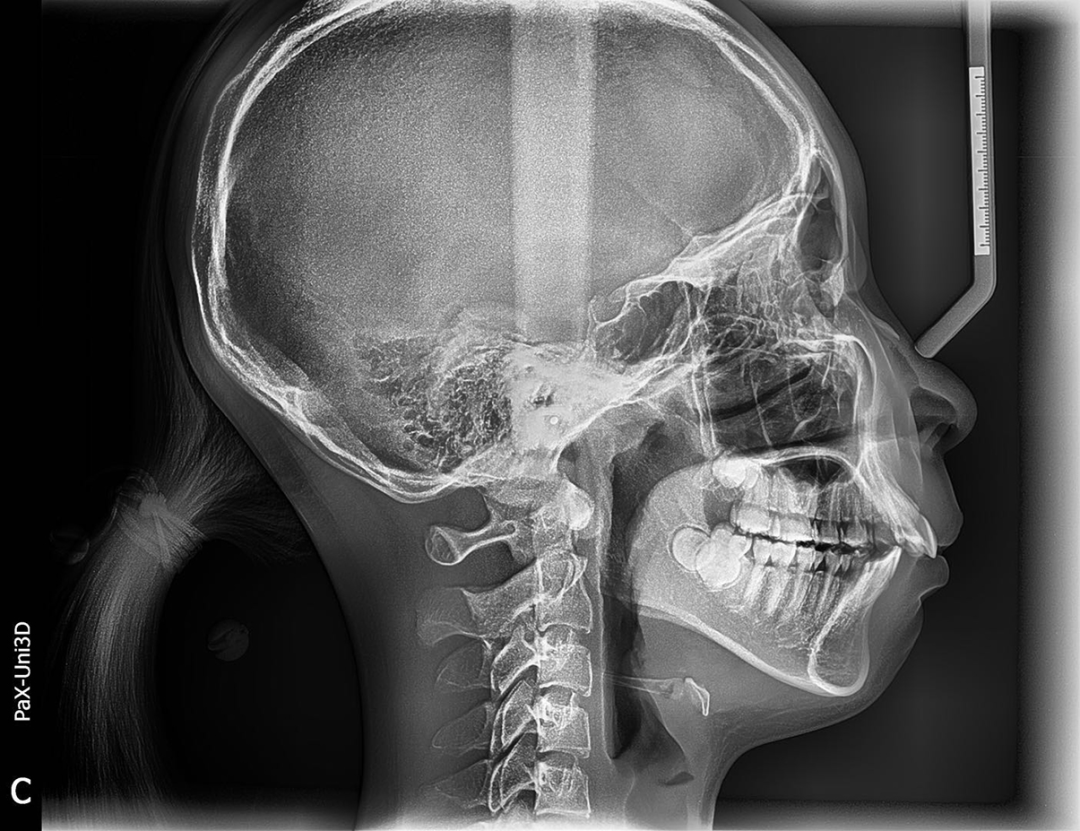

一般在替牙中期孩子上下4颗门牙换完,是比较好的干预时机,再就是女孩替牙晚期,只剩上下第二乳磨牙还没有脱落;男孩刚刚结束替牙期,正处于年轻恒牙列阶段,还有机会引导下颌向前生长。